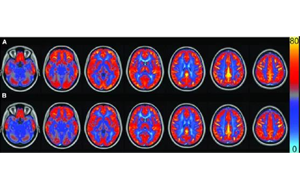

AJCN:要長壽,常吃豆!長期食用大豆飲食可讓大腦“更靈光”

俗話說,寧可一日無肉,不可一日無豆,俗話還說,每天吃豆三錢,何需服藥連年。作為一種理想的營養物質,大豆食品在平衡膳食中至關重要。科學家們已經發現,大豆具有幫助減肥、美化皮膚、預防生活習慣病、防止骨質疏松癥等重要作用,然而,目前尚無關于大豆在調節大腦血管功能方面的研究。